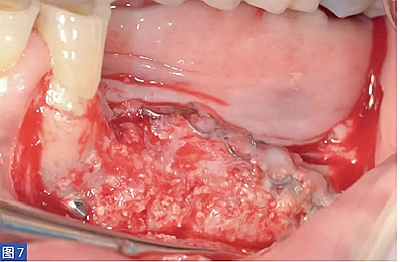

圖7:(右側(cè))病例1. 術(shù)后6 個(gè)月的再生組織。

圖8:病例1. 術(shù)后6 個(gè)月的再生組織。咬合面觀。